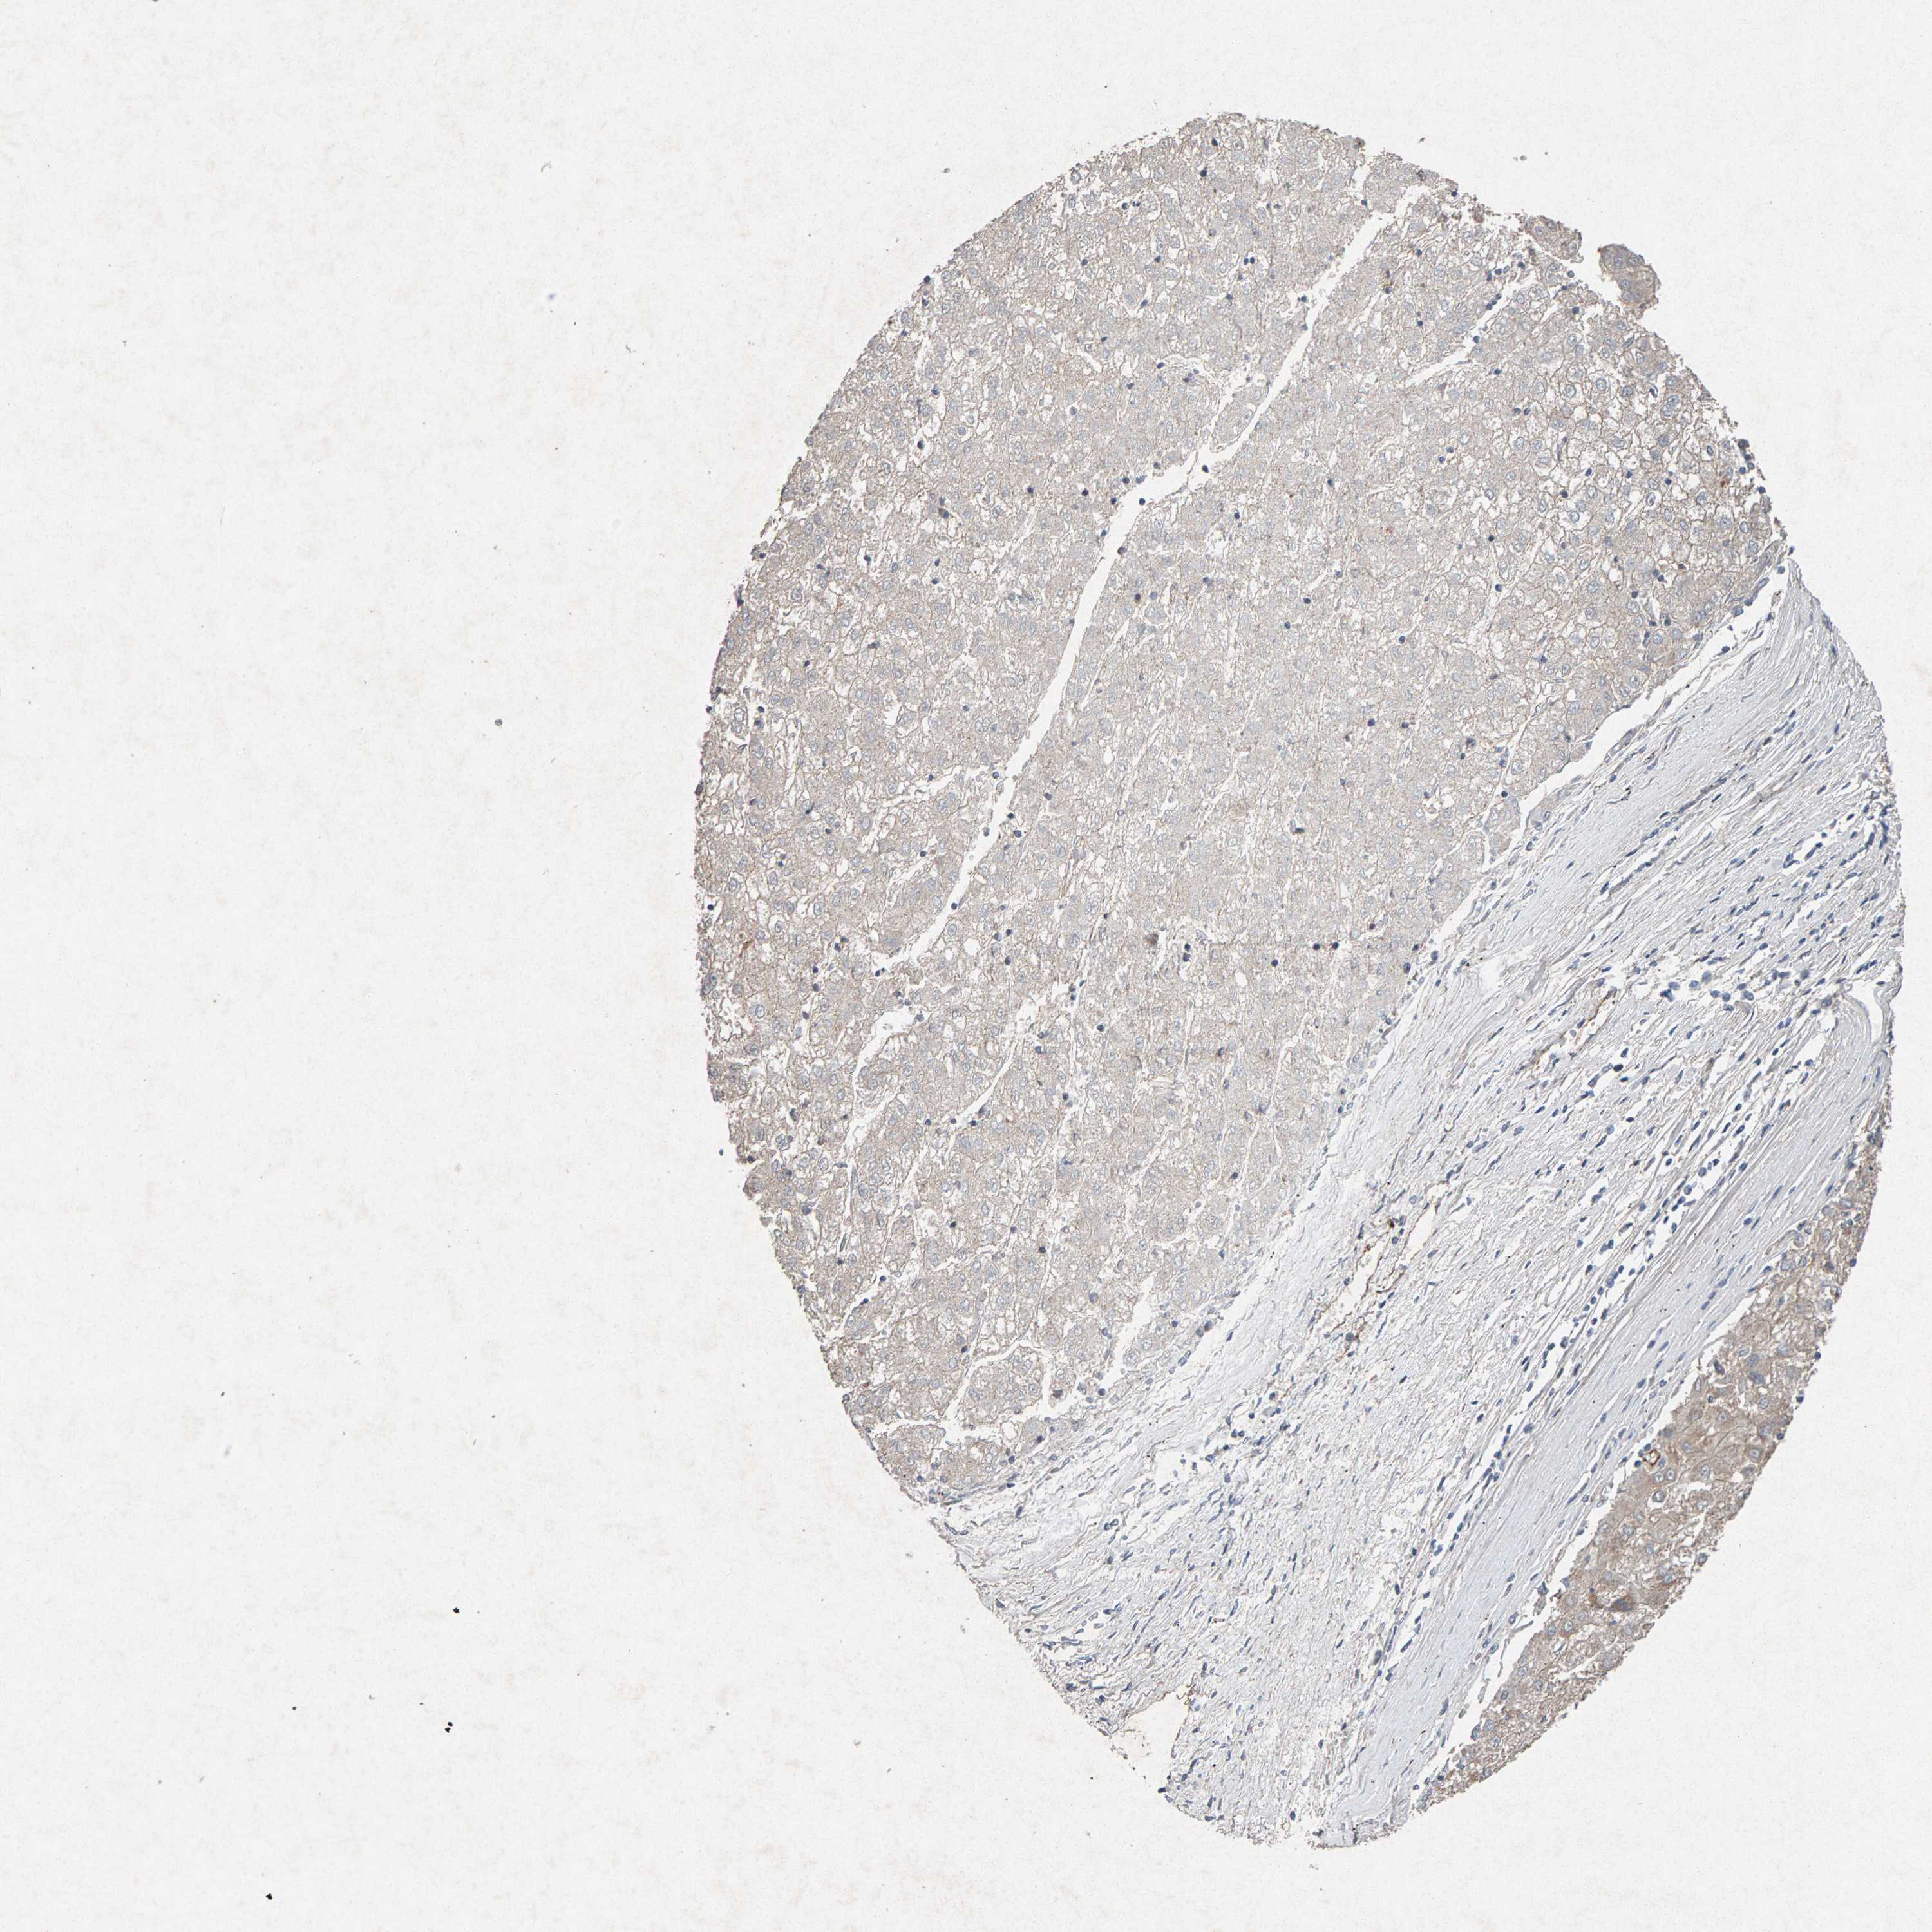

LIVER CANCER - Protein expressioni

A mouse-over function shows sample information and annotation data. Click on an image to view it in a full screen mode. Samples can be filtered based on level of antibody staining by selecting one or several of the following categories: high, medium, low and not detected. The assay and annotation is described here.

Note that samples used for immunohistochemistry by the Human Protein Atlas do not correspond to samples in the TCGA dataset.

Antibody stainingi

Antibody staining in the annotated cell types in the current human tissue is reported as not detected, low, medium, or high, based on conventional immunohistochemistry profiling in selected tissues. This score is based on the combination of the staining intensity and fraction of stained cells.

Each image is clickable and will lead to virtual microscopy that enables deeper exploration of all samples and also displays staining intensity scores, fraction scores and subcellular localization as well as patient and tissue information for each sample.

Antibody CAB022442

Antibody CAB022443

Staining

Cholangiocarcinoma

Carcinoma, Hepatocellular, NOS